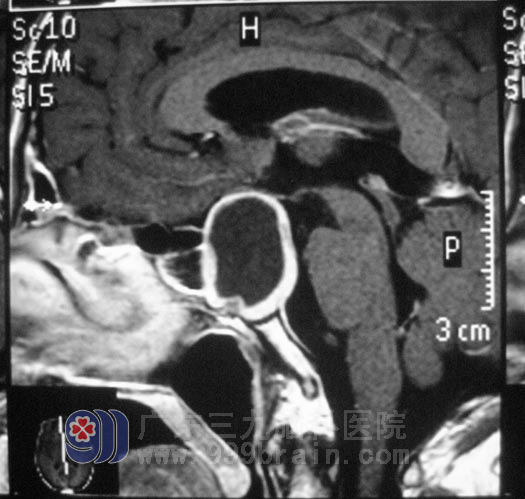

9月下旬,邱先生入住广东三九脑科医院垂体瘤诊疗中心,头颅MR检查提示占位大小约为2.5cm×3.0cm×3.3cm。考虑到邱先生的甲亢病史,在严密监测其基础代谢率及内分泌的改变都正常后,邱先生在全麻下行经鼻蝶鞍区肿瘤切除术,右侧鼻孔入路,导航定位,暴露蝶窦后见肿瘤呈灰白色,质软,血供一般,在显微镜下予肿瘤切除,术中未损伤到垂体,术后未出现脑脊液漏、尿崩等并发症,经过一周的治疗,邱先生康复出院。术后病理结果为:(鞍区)垂体腺瘤,FSH(+)。

▲手术前MR